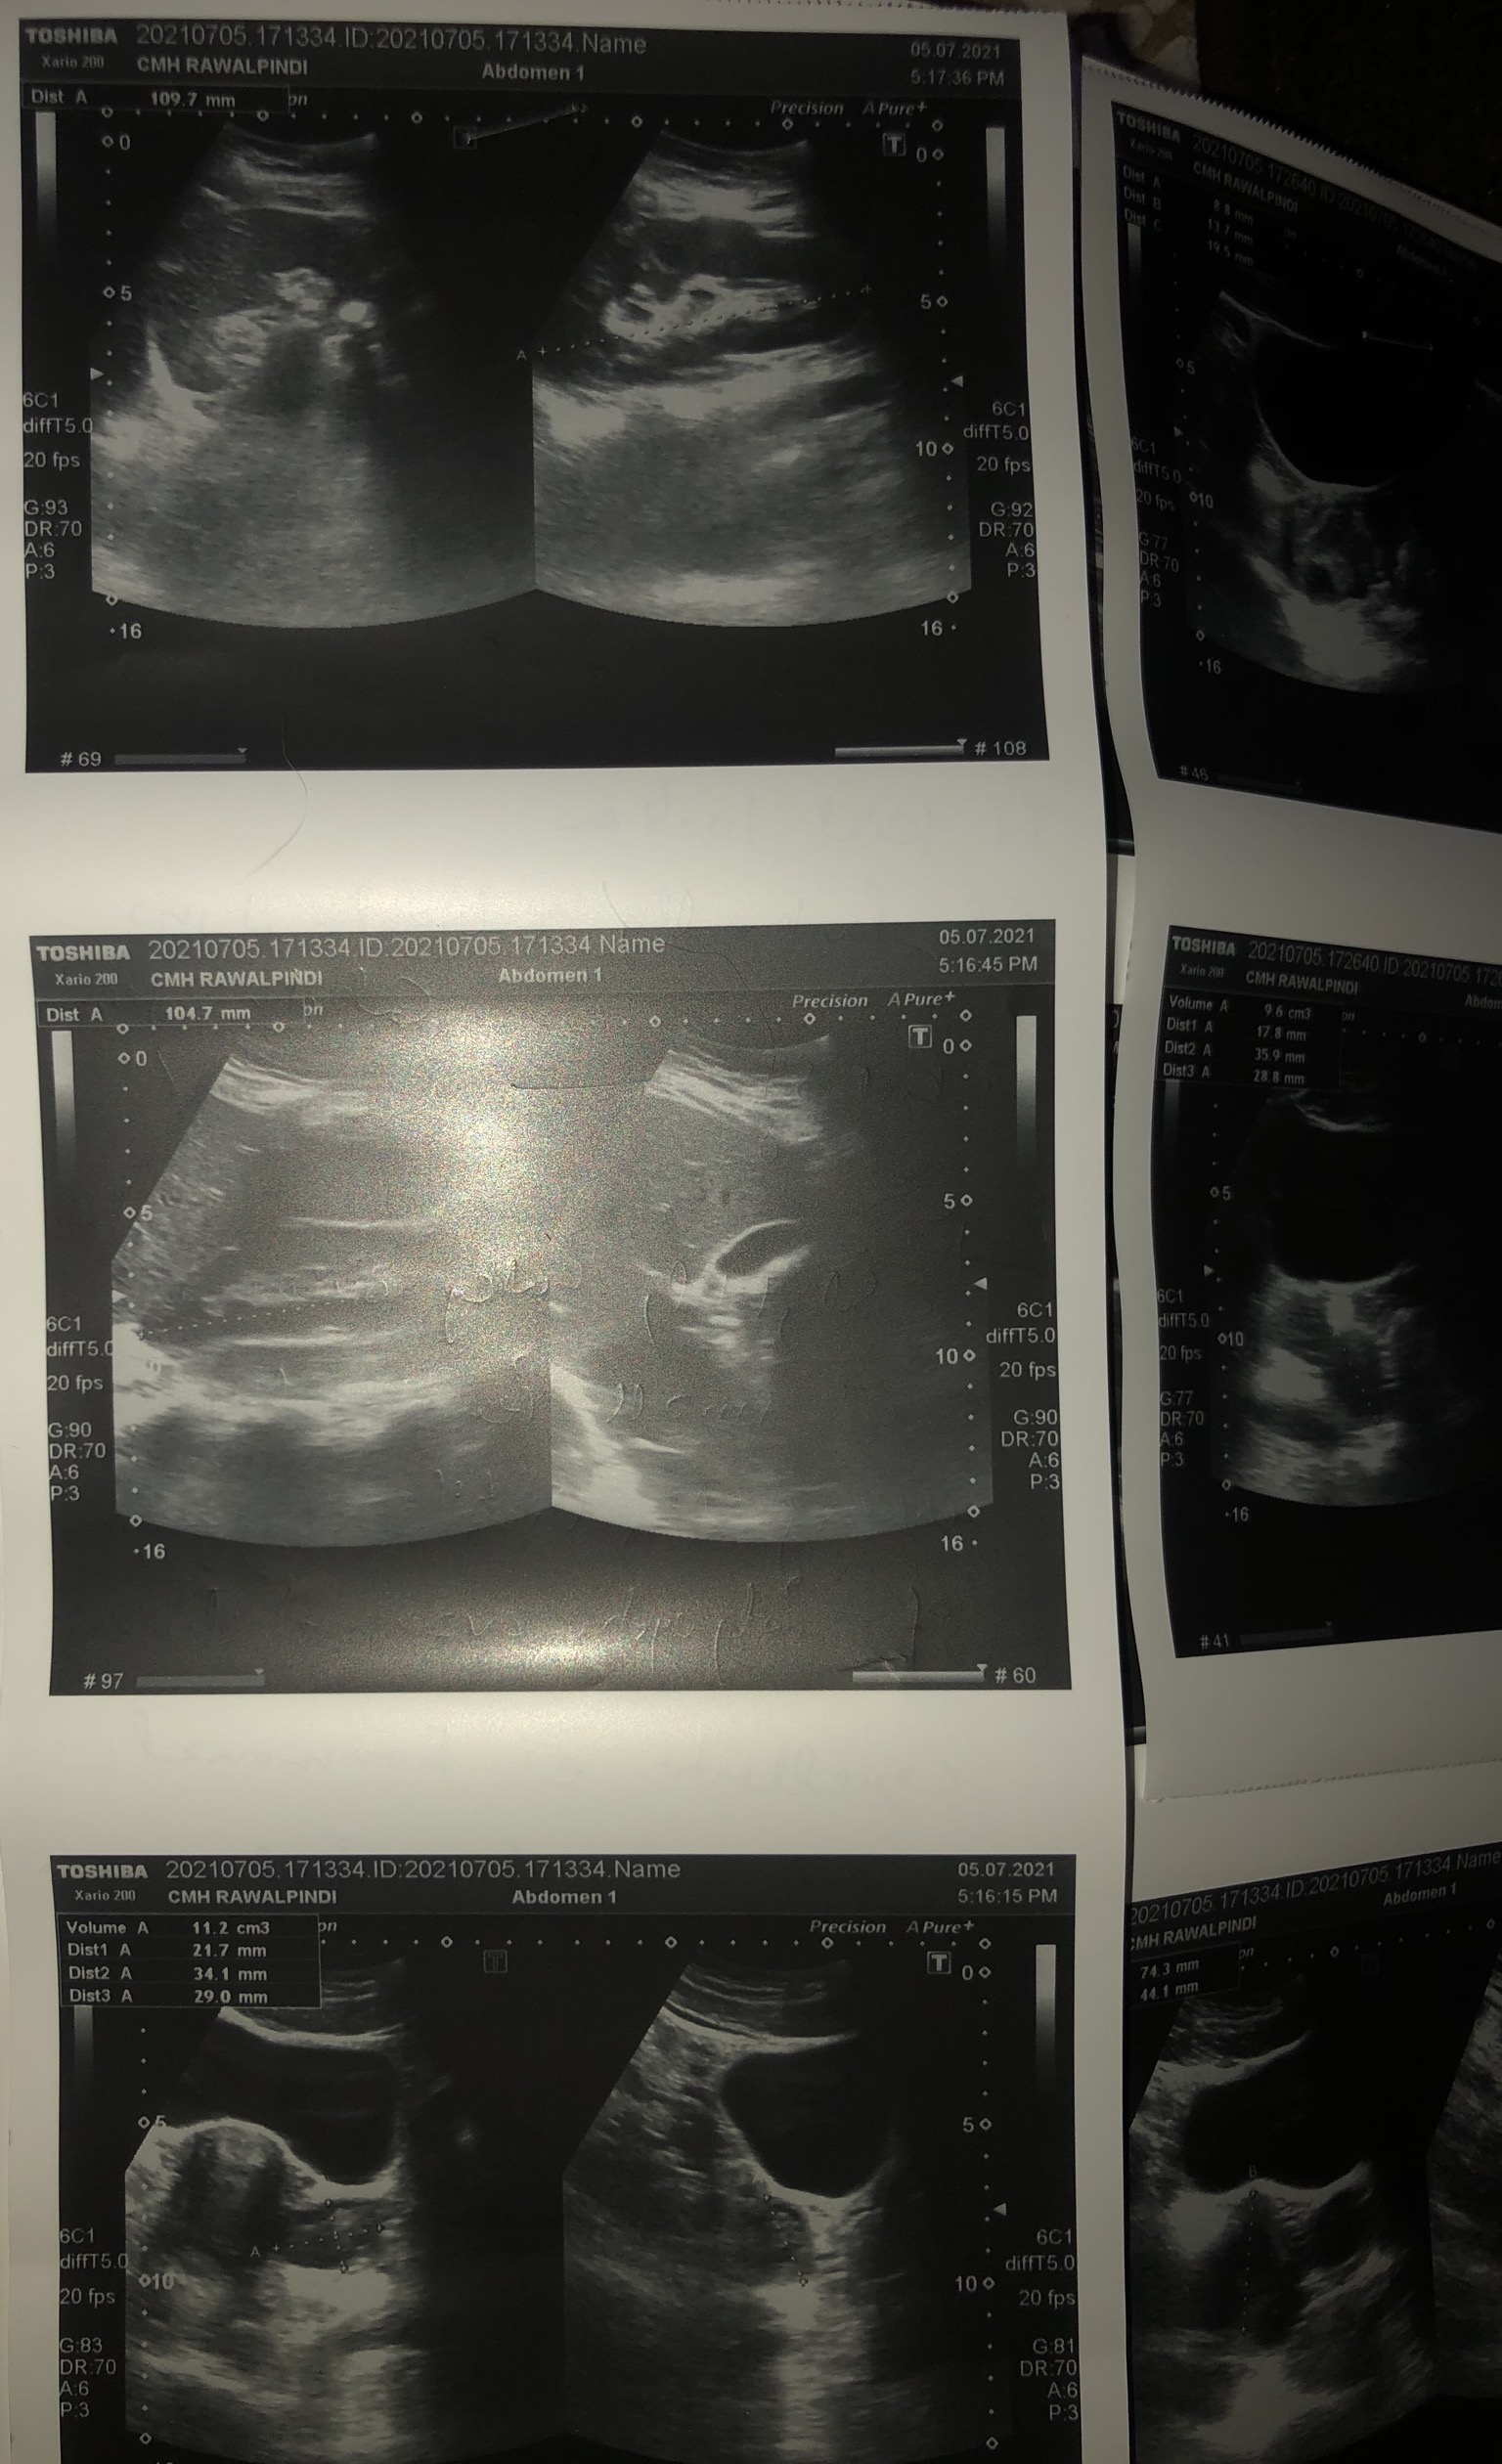

Asking for Self, Female, 28 years old, Rawalpindi

Plz help read my repirts and any treatment

Aoa your scan report and periods pattern suggestive of pcos. You need diet exercise and consultation. So you can understand and manage your problem. Thank you

go for hormonal profile...then for suitable treatment see ur gynaecologist...meanwhile weight loss,exercise etc are advisable